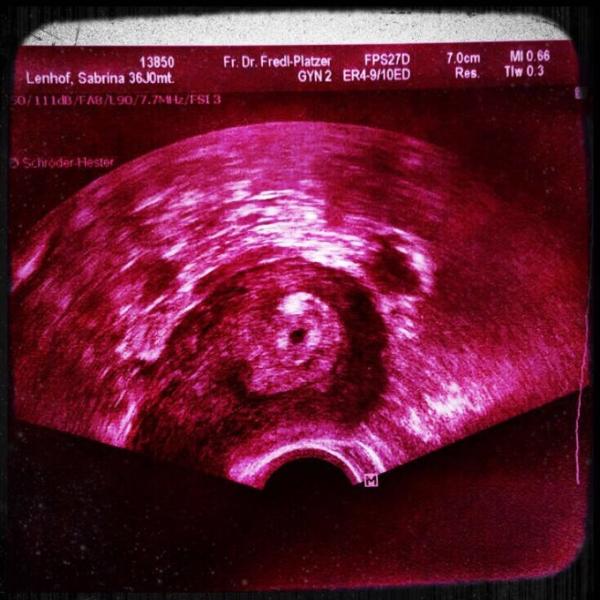

Hallo ihr Lieben, meine 1 icsi stellt sich als Krimi raus An Transfer + 20 stellte sich heraus ( 2.11 ) das ich schwanger bin..Hcg bei 107 am 10.11 hatte ich dann meinen ersten US Termin. Man sah nichts... Hcg war auf 1688 gestiegen.. Verdacht auf ELS, die sich am gleichen Tag nach Bauchspiegelung nicht bestätigte. Die Ärztin machte mir allerdings keine großen Hoffnungen und sagte sogar sie würde ohne mit der Wimper zu zucken eine Ausschabung machen. Ich habe mich dann auf eigenen Wunsch entlassen. Fand es echt heftig. Der Hcg war dann am 13.11 auf 1906 angestiegen und seit dem 16.11 auf 2700. Gestern sah meine Ärztin dann endlich die Fruchthöhle von 4 mm. Habe mich soooo gefreut und die Ärztin auch. Hatte jemand von euch ähnliche Erfahrungen und die Schwangerschaft hat sich gut entwickelt?

Bild zu Bibbern nach pos Test - Kinderwunschbehandlung